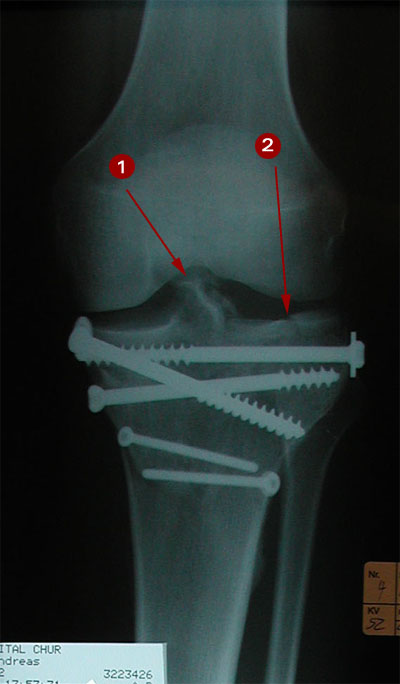

Die gute Nachricht: Im Röntgenbild vom 5. Juli sind kritische Bereiche des Kniegelenks wieder fast intakt, so z.B. die im unteren Bild (vom 23. Mai) sichtbare Frakturstelle in der Gelenkfläche (2) sowie Teile der Eminenz (1). Die Kreuzbänder scheinen jedenfalls wieder zu halten.

Dazu als Vergleich das Röntgenbild vom 23. Mai 2001; Beginnende Einheilung der Emimnenz (1) sowie deutliche Frakturstelle in der Gelenkfläche (2).